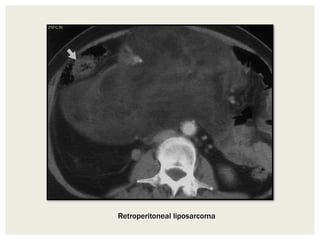

Retroperitoneal liposarcoma

Liposarcomas

• Most common primary retroperitoneal malignant tumor,

typically occuring in the 5th and 6th decades of life, with a slight

female predilection.

• Classified at pathologic analysis into well-differentiated

(lipogenic), pleomorphic, myxoid, and dedifferentiated types.

• Well-differentiated liposarcomas usually contain an appreciable

amount of fat with varying amount of enhancing soft tissue

density components, and merging imperceptibly with adjacent

normal fat and displacing rather invading adjacent organs.

• Undifferentiated liposarcomas may not demonstrate

appreciable fat, and are indistinguishable from non fatty soft

tissue sarcomas.